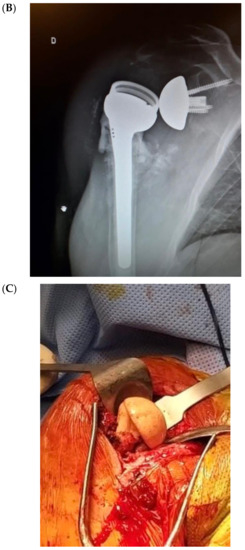

Figure 4 illustrates an infected case of proximal humerus fracture sequelae, originally treated with a plate, then treated according to our protocol. After plate removal, an RSA was implanted, which subsequently dislocated, resulting in infection. A two-stage procedure was performed: removal of the RSA, debridement, and implantation of a cement antibiotic spacer with vancomycin. MicroDTTect identified the pathogen (Cutibacterium acnes), intravenous antibiotics and infection eradication followed.

Figure 4.

(A) The X-ray of a case of an infected proximal humerus fracture sequelae, originally treated with a plate. (B) After plate removal, the first RSA was implanted, which subsequently dislocated, resulting in infection. (C) A two-stage procedure was performed: removal of the RSA, debridement and implant of a cement antibiotic spacer with vancomycin. (D) Spacer X-ray postoperative image.

Similar to the cited hybrid technique used in knee revision, three procedures for shoulder arthroplasty revision with consistent metaphyseal bone loss were conducted, employing the bioactive glass and tantalum cones. Two of these were the result of two-stage surgeries after PJIS.

The senior shoulder surgeon (AMR) implanted an RSA using the Equinoxe Shoulder System (Exactech Inc., Bloomington, MN, USA). The humeral canal was sized and then compacted until rotational stability of the trials was achieved and a longer cemented stem was required. The glenosphere diameter was 42 mm.

A porous tantalum cone (Zimmer, Warsaw, IN, USA) was employed for extensive defects of humeral metaphyseal bone. Bioactive glass was added both between the stem and cones, and as a proximal humerus augmentation (Figure 5 and Figure 6) in order to improve defect filling and attempt to avoid a new infection, thus increasing implant stability and integration. The surgical technique has already been described in detail [48]. The high porosity of these cones results in satisfactory primary fixation on recipient bone and cement fixation on the intramedullary side, sealing the component. Local filling of metaphyseo-diaphyseal bone defects with cones can limit the use of massive allografts or tumoral prostheses.

Figure 5.

(A,B) In the second stage surgery, a femoral diaphysis tantalum cone was inserted in the proximal humerus with a cemented stem RSA. (C,D) Finally, bioactive glass proximal augmentation was performed.